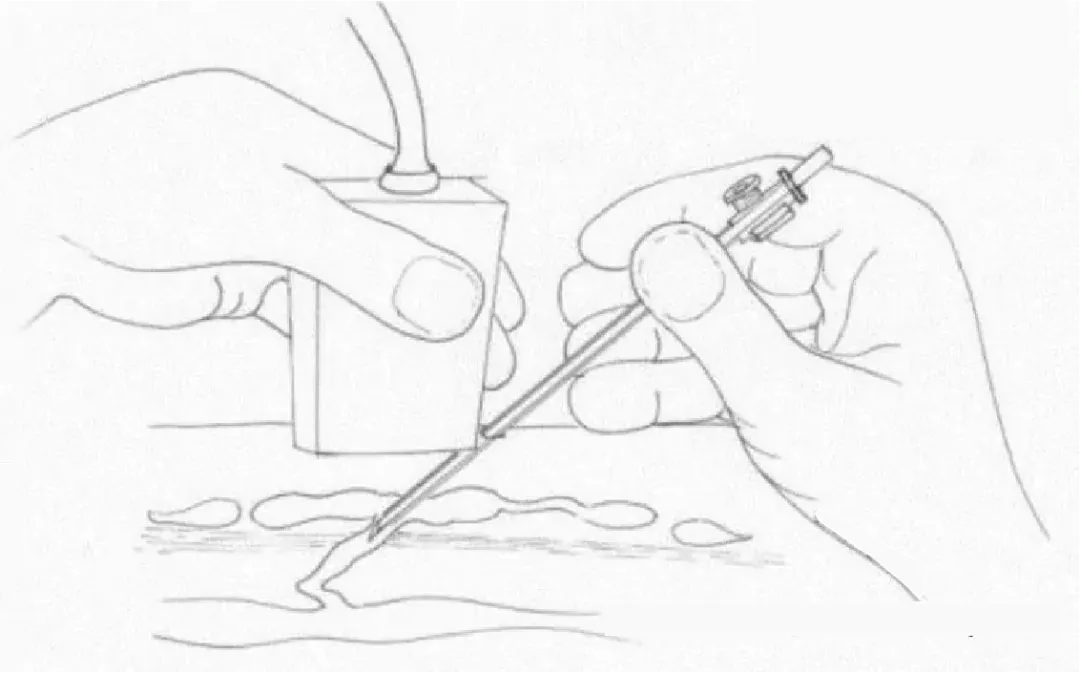

许多医生忽略了作为静脉反流模式的一部分的IPV。1985年以前,除了开放结扎术外,没有其他治疗方法。然而,1985年Hauer发明了筋膜下内镜穿支静脉(subfascial endoscopic perforating vein, SEPS)手术,将内镜引入膝下筋膜下间隙,在筋膜下夹闭静脉。然而,SEPS仍需要2 ~ 3 cm的切口,通常需要全身麻醉,术后肌肉操作带来的不适较多,且穿支血管的处理局限在小腿内侧。2000年,发明了经腔穿支静脉闭塞 (TRansluminal Occlusion of Perforators, TRLOP) 手术。

在超声控制下,对IPV进行插管,并在穿支置入消融装置。最初使用射频,后来使用腔内激光。TRLOP在2007年被“重新定义“为“穿支消融术“ (PAPS),尽管两种技术之间没有任何差异。其他工作者通过注射氰基丙烯酸酯胶进一步改进了这一点。TRLOP方法可与这些方法中的任何一种一起用于IPV的局部消融,即使静脉较短。

超声引导下经腔穿支静脉闭塞 (TRansluminal Occlusion of Perforators, TRLOP) 手术。